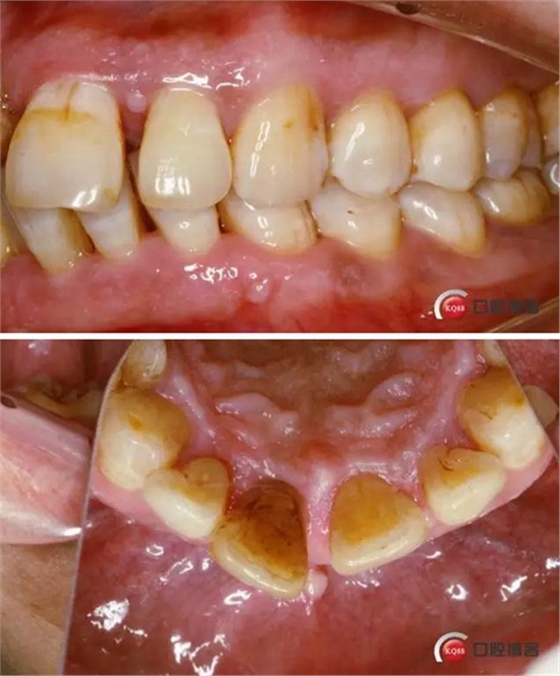

患者:王XX 年齡:42 上前牙松動數(shù)年,從未做過任何處理,今來院就診;檢查:CBCT示上前牙區(qū)顎側(cè)一大小約7x7mm囊腫;治療計劃:即刻種植同期摘除囊腫

術前口內(nèi)照